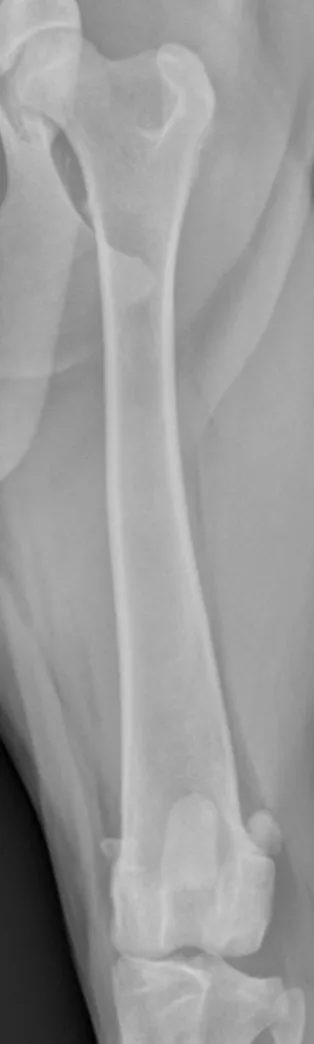

With a straight craniocaudal femoral radiograph, the tip of the lesser trochanter should be visible on the medial side of the proximal femur (A); the medial (B) and lateral (D) fabellae should be equally positioned over the medial and lateral femoral cortices, but there can be some variation among patients. The patella (C) should be centered over the distal femur, and both sides of the intercondylar notch should be parallel and visible (parallel lines).